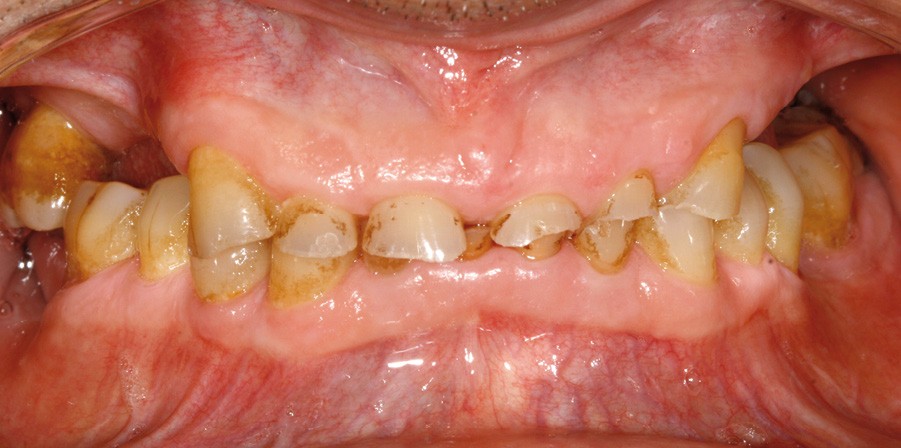

• L’examen intrabuccal montre de nombreux édentements non compensés (14, 15, 16, 24, 25, 26, 27, 47 et 36) ainsi que des pertes de substance très importantes, notamment dans le secteur antérieur.

Une attrition sévère, couplée à une occlusion sans calage postérieur, a engendré des difficultés pour s’alimenter.

• Le bilan esthétique nous indique plusieurs points disgracieux :

– dysharmonie des contours gingivaux (ligne des collets) avec une ligne du sourire basse [1] ;

– perte de substance extrême du bloc incisivo-canin maxillaire et des incisives mandibulaires ;

– visibilité très limitée des dents lors d’un sourire forcé ;

– égressions compensatoires.